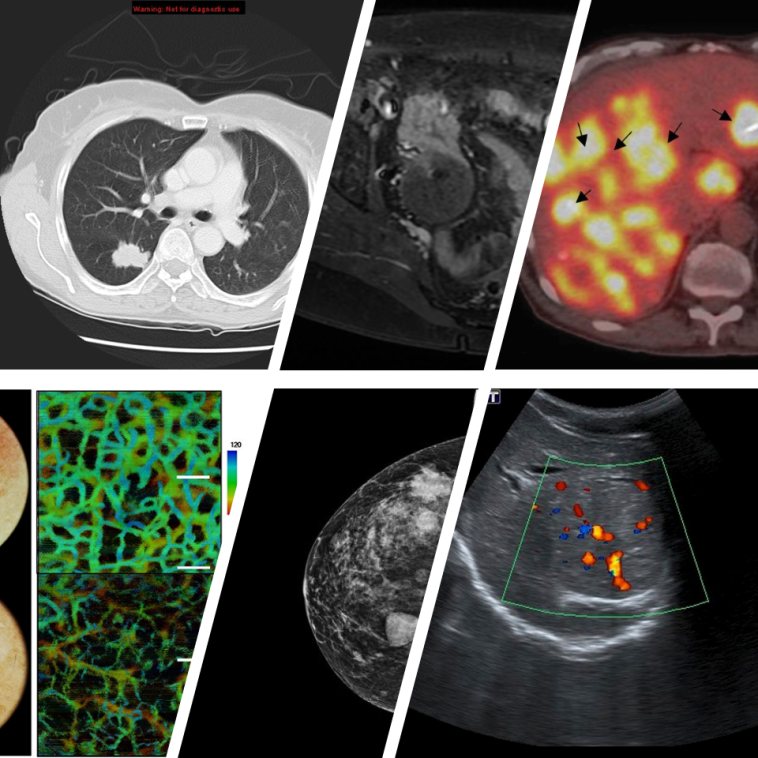

Breast Imaging: Modern Approaches for Early Detection

Early detection is key when figuring a path to better health, and breast imaging stands as one of the most super important tools in this battle. At centers such as Fred Hutch, the use of 3D mammography, or digital breast tomosynthesis, means that images are captured layer by layer, enhancing the view of the breast tissue in a way that traditional techniques cannot match.

This process involves using X-rays to create detailed shots of the breast. The technology is built to enhance the subtle parts of an abnormal tissue by superimposing several layers of images. Occasionally, the imaging process may require a contrast agent – a substance that is introduced into the body to reveal otherwise hidden details. In some cases, a breast magnetic resonance imaging (MRI) scan is used, offering another angle to get into the nitty-gritty of breast tissues, particularly in complex cases.

- 3D Mammography: Offers a layered view of tissues for better early detection.

- Breast MRI: Uses magnetic fields instead of X-rays and is ideal for patients with dense breast tissue.

- Breast Ultrasound: Provides additional insights, especially when trying to figure out if a mass is solid or filled with fluid.

Computed Tomography (CT) Scan: A Closer Look at Internal Structures

The CT scan is another cornerstone of modern diagnostic imaging. Using a special X-ray machine, CT scans take detailed cross-sectional images that portray both organs and bones with fine shades of detail. For anyone dealing with cancer, seeing organs clearly can be the difference between early detection and a delayed diagnosis.

Before the procedure, a contrast material may be administered to spotlight blood vessels and tissues. This helps doctors figure out a detailed map of the area, making it easier to design personalized treatment plans. In fact, many cancer patients undergo CT scans not only for initial assessment but also for planning subsequent treatments like radiation therapy. When it comes to certain cancers, low-dose CT scans have become a super important screening tool, particularly for those at high risk of lung cancer.

Magnetic Resonance Imaging (MRI): The Magic of Magnets

MRI offers a different approach by using powerful magnets and radio waves to capture detailed 3D images. Unlike CT scans, the MRI is best at revealing soft tissues, which can be challenging to see on traditional X-ray images. The subtle parts of tumors sometimes hide in these soft tissues, and an MRI can uncover those hidden complexities.

Nuclear Medicine: Seeing Beyond Structure Into Function

Nuclear medicine represents a fascinating marriage between imaging and molecular science. In this technique, a small dose of a radioactive substance is introduced into the body. As it travels through the system, it gathers in areas that may indicate disease. The subsequent scans—often a PET/CT or PET/MRI—bring a dual dimension to imaging: they show both the structure and the function of tissues.

This combination can help doctors observe how cancer cells behave compared to healthy cells. The technique is especially helpful for those undergoing molecular therapies, where higher doses of radiation are targeted directly at tumor cells. The result is an informative picture that guides treatment and monitors progress over time.

Integrating Multiple Modalities for a Complete Picture

One of the remarkable achievements in modern radiology is the integration of various imaging methods into a cohesive diagnostic approach. Each technique offers a unique window into the human body, and when combined, these techniques can provide a full spectrum of information crucial for cancer care.

Consider how these imaging modalities complement each other:

| Imaging Modality | Key Benefit | Use in Cancer Care |

|---|---|---|

| 3D Mammography | Layered high-resolution images | Early breast cancer detection |

| CT Scan | Detailed cross-sectional views | Staging and monitoring treatment effects |

| MRI | Contrast-rich soft tissue images | Identifying tumors hidden in soft tissues |

| Nuclear Medicine | Functional imaging | Tracking metabolic activity in cancer cells |

| Interventional Radiology | Real-time, image-guided procedures | Minimally invasive biopsies and treatments |

This table illustrates just a few examples of how different imaging techniques can work in tandem. When patients are guided through this array of tools, they benefit from the fusion of structure and function data, leaving little room for the distracting bits of misinterpretation.